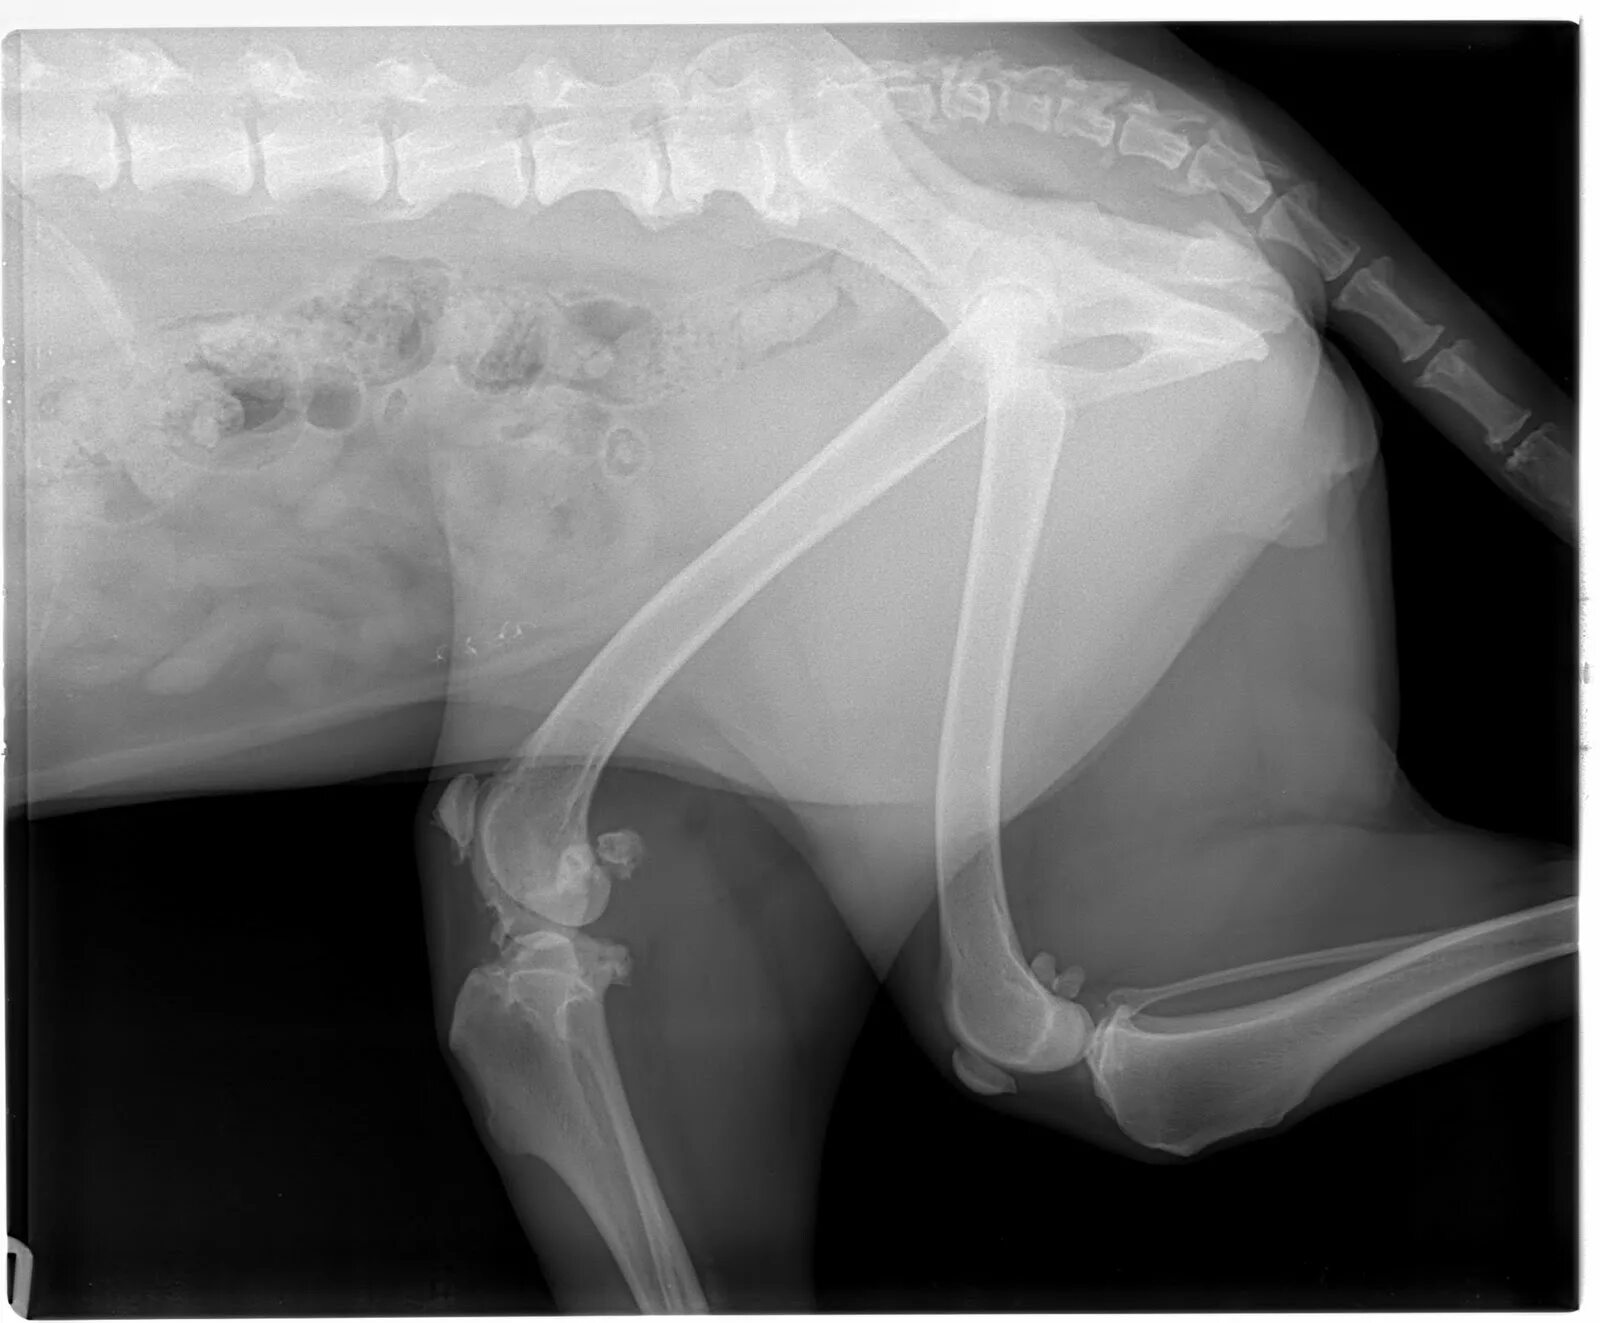

Операция суставов собак